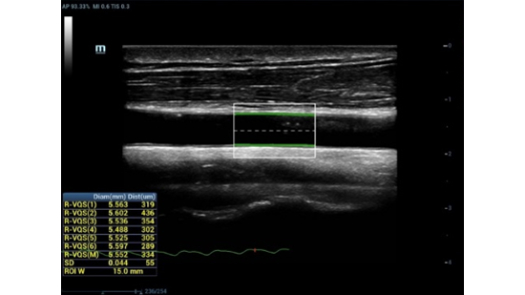

Pencitraan Tepercaya

MX7, berdasarkan platform ZST + revolusioner kami, teknologi probe premium, dan algoritme canggih, dirancang untuk memberikan pencitraan tepercaya bagi dokter, memberikan lebih banyak kepercayaan pada diagnosis.